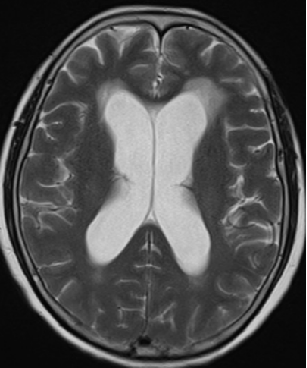

2013-5-16 MRI